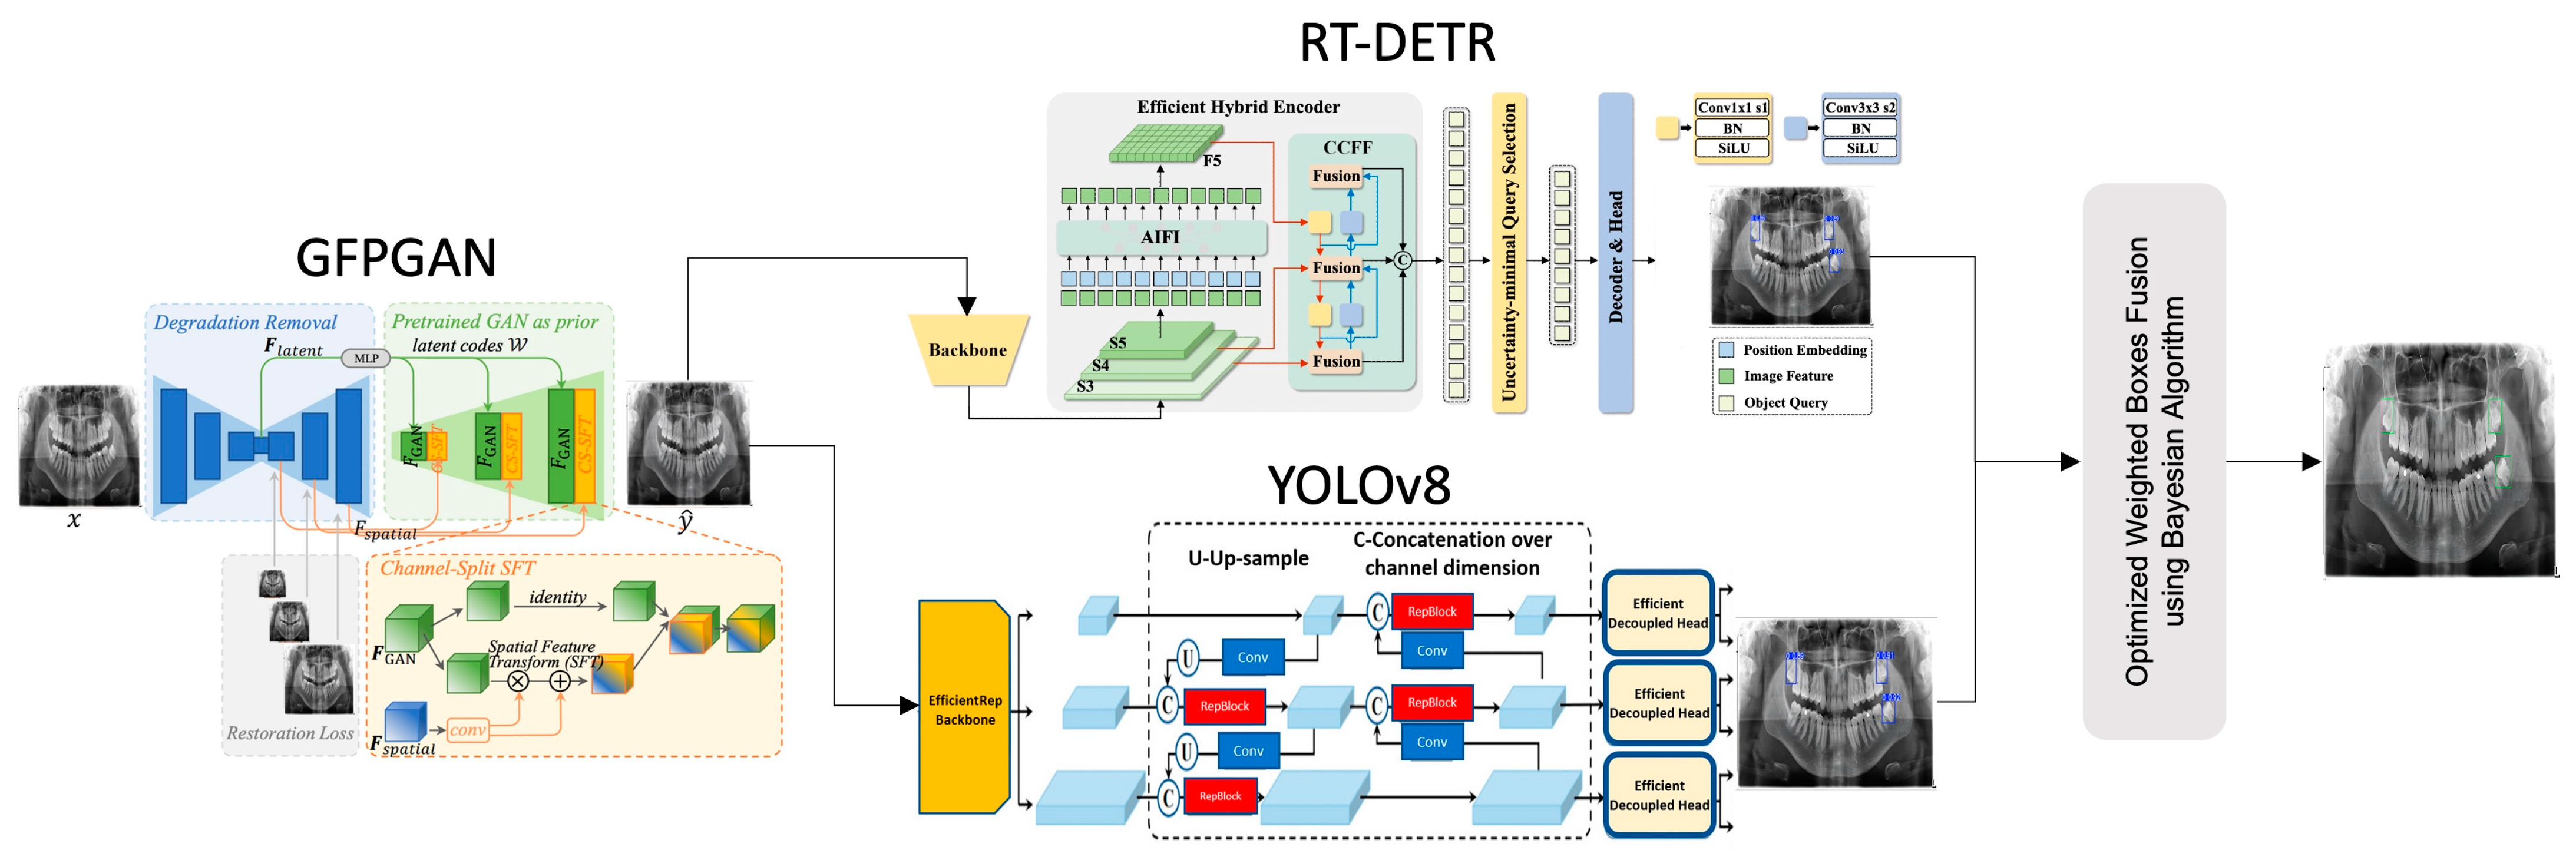

2. Materials and Methods

- The Generative Facial Prior (GFP-GAN) module improves the clarity of the input image by enhancing low-resolution panoramic images with a super-resolution method. This process provides higher quality data for the next steps and contributes significantly to the overall performance of the model. GFP-GAN reconstructs the detail in low-resolution images, producing a sharper and more meaningful input.

- In the second phase, the RT-DETR module uses a transformer-based approach to regionally detect dental structures in panoramic images. This module extracts meaningful features from complex image structures and accurately labels target regions. In particular, it provides high accuracy in dental radiographs thanks to its ability to model sequential relationships and improve positional accuracy.

- In the third stage, the YOLOv8 model classifies the detected tooth regions in detail and marks them more precisely. YOLOv8 is one of the most efficient object detection algorithms, delivering fast and accurate results. This component allows detailed analysis of important structures in dental radiographs and optimizes the detected areas, improving overall accuracy.

- In the final stage, the detection results from the different modules are combined with the WBF method, enhanced with Bayesian optimization. This method combines the strengths of the models and provides a more accurate and integrated output. By combining the predictions of different modules, WBF minimizes the false positive and false negative rates. Finally, the analysis of the dental structures is complete, and the results are presented with high accuracy.

2.1. Generative Facial Prior

2.2. CNN (YOLO)

2.3. Transformer (RT-DETR)

2.4. Ensemble Strategy